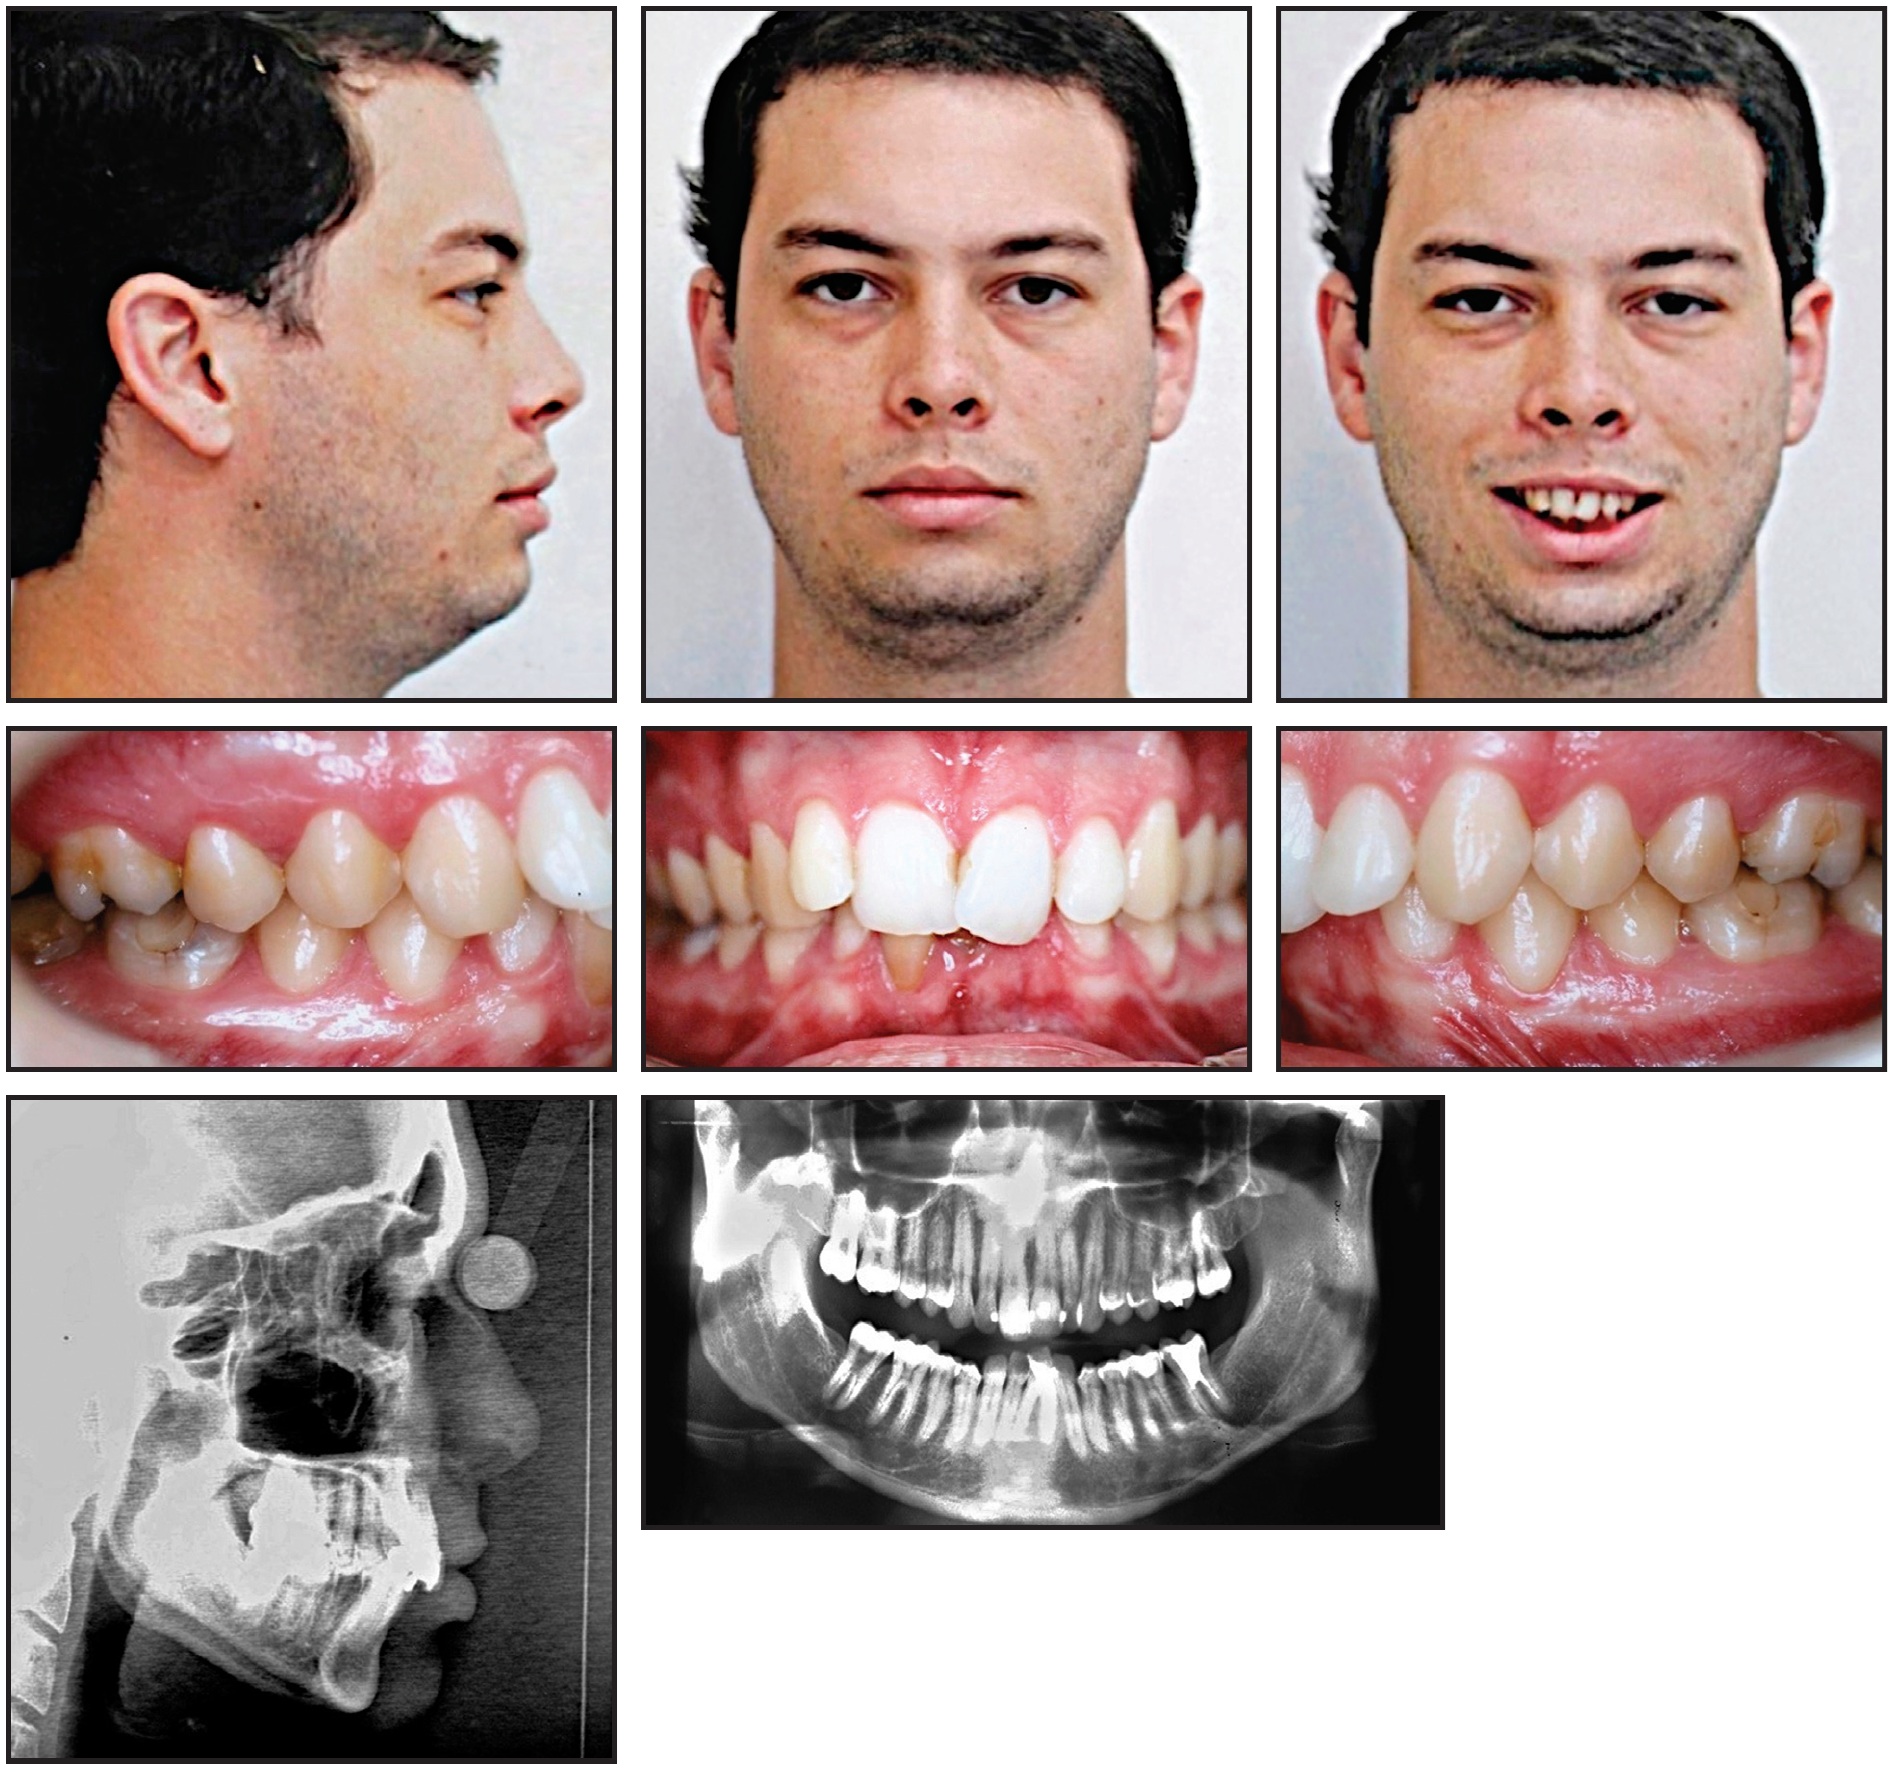

A 25-year-old male presented with the chief complaint of crowding in the mandibular anterior segment, including a complete lack of space for two mandibular incisors (Fig. 1A). He exhibited a balanced facial profile, Class I molar and canine relationships, somewhat narrow maxillary and mandibular arches, crowded upper incisors, and severely crowded lower incisors (Fig. 1B).

Fig. 1 25-year-old male patient with lower anterior crowding, Class I molar and canine relationships, skeletal Class II relationship, and severe overbite and overjet before treatment (continued in next image).

Fig. 1 (cont.) 25-year-old male patient with lower anterior crowding, Class I molar and canine relationships, skeletal Class II relationship, and severe overbite and overjet before treatment.

Cephalometric analysis indicated a Class II skeletal relationship with a slightly protrusive maxilla and a slightly retrusive mandible (Table 1). The overjet and overbite were extreme because of the lower crowding. The maxillary incisors were vertically inclined and slightly retrusive, while the mandibular incisors were labially inclined and protrusive. The nasolabial angle was within the normal range. A panoramic radiograph confirmed the absence of the third molars, which had been extracted previously.